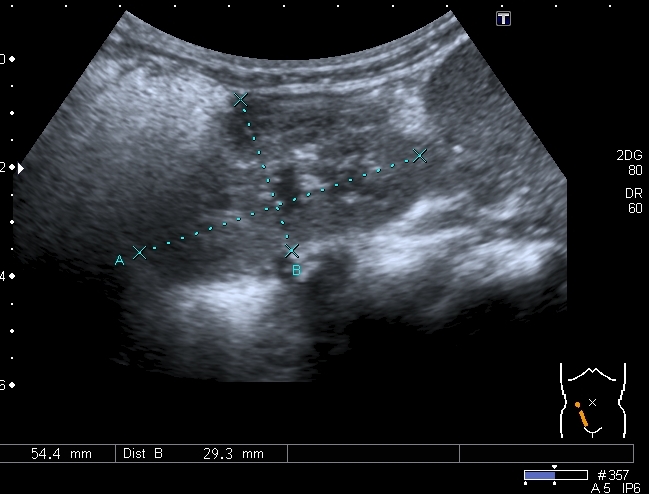

В хирургический приёмный покой поступил ребёнок 2-х лет с жалобами родителей на увеличение живота. Направлен на УЗИ с диагнозом "Опухоль Вильмса справа?"

При осмотре - живот увеличен в размерах, в правой половине пальпируется плотное образование.

При УЗИ вся правая половина живота выполнена солидно - кистозным образованием больших размеров.